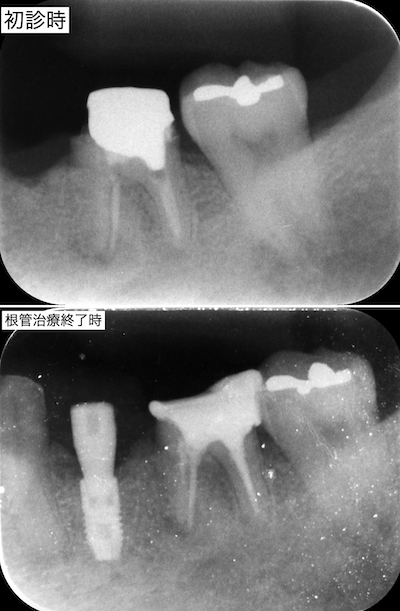

患者さんはインプラント治療を選択されたので、手術計画書を作成しました。治療期間に無駄がないように奥歯の根管治療はインプラントの骨結合の待機期間で行う事としました。

インテグレーションを待つ2ヶ月の間に、根管治療を行いました。その後、2次手術を行い、仮歯を適合させました。